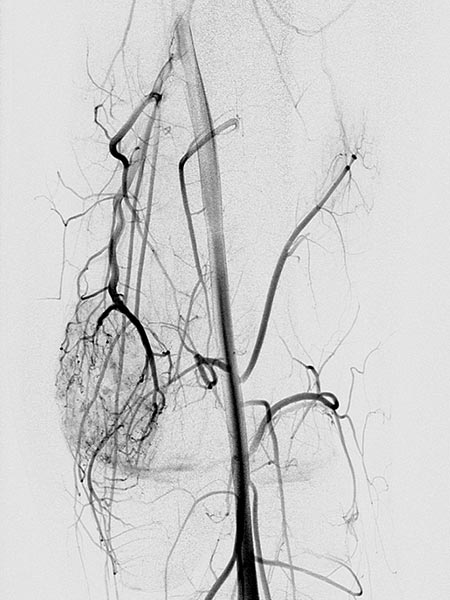

Digital subtraction angiography (DSA) in the early arterial phase shows a dilated feeding artery (so-called “feeder artery”), in this case a medial superior genicular artery. This artery is dilated over time due to chronic hyperperfusion with increased blood flow.

Digital subtraction angiography (DSA) in the arterial phase 2 s later shows some minor arteriovenous fistulas.

Digital subtraction angiography (DSA) in the interstitial and early venous phase again 4 s later shows no direct early venous outflow of the contrast agent but, instead, a pooling phenomenon. In an arteriovenous malformation, an immediate venous outflow would be seen because of multiple direct arteriovenous communications.

Super-selective catheterization of the feeding artery with a microcatheter again depicts multiple, fine arteriovenous fistulas, but not the immediate venous outflow as would be typical of an AVM. However, the visible arteriovenous fistulas are unusually prominent in this venous malformation.